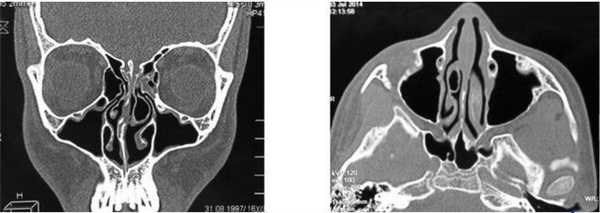

На снимке концентрическая воспалительная гипертрофия (указана стрелками) слизистой оболочки гайморовых пазух

Концентрическая воспалительная гипертрофия ячеек решетчатой кости (указана стрелками)

Слева — КТ-снимок одонтогенной кисты в верхнечелюстном синусе, справа — МР-фото образования (указано стрелкой) в гайморовой пазухе